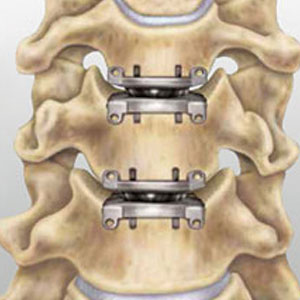

• Disc replacement: Replacing the injured disc with an artificial one.